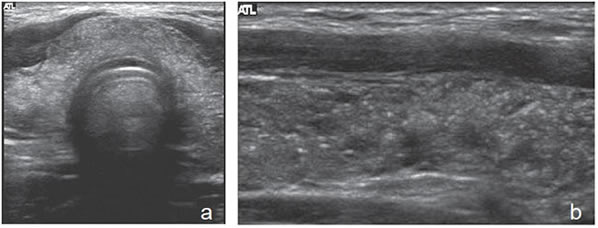

Patrón indeterminado o neoplásico

Son tumores sólidos, únicos, iso o hiperecogénicos, muy homogéneos, encapsulados, de contornos lisos, de forma ovoidea, sin microcalcificaciones (Figura 3b). En el 80% de los casos se puede observar un halo hipoecogénico. Ocasionalmente pueden ser discretamente hipoecogénicos. La vascularización habitualmente esta aumentada en la periferia con vasos que se descuelgan hacia el centro de la lesión (Figura 12). A diferencia de los nódulos coloideos generalmente no se observan imágenes quísticas (Figura 32).

En este grupo se encuentran principalmente las neoplasias foliculares benignas (adenomas) o malignas (carcinomas). Están compuestos de células foliculares o células de Hurthle en distinta proporción, y son encapsuladas. La mayoría (85%) corresponden a adenomas foliculares. Sin embargo, con el mismo patrón se puede presentar el carcinoma folicular bien diferenciado, aunque este suele ser de mayor tamaño, hipoecogénico, de contenido más heterogéneo, la capsula de mayor espesor (Figura 33a y b) y el aumento de la vascularización es difuso22. La presencia de calcificaciones intranodulares conlleva mayor riesgo de malignidad.